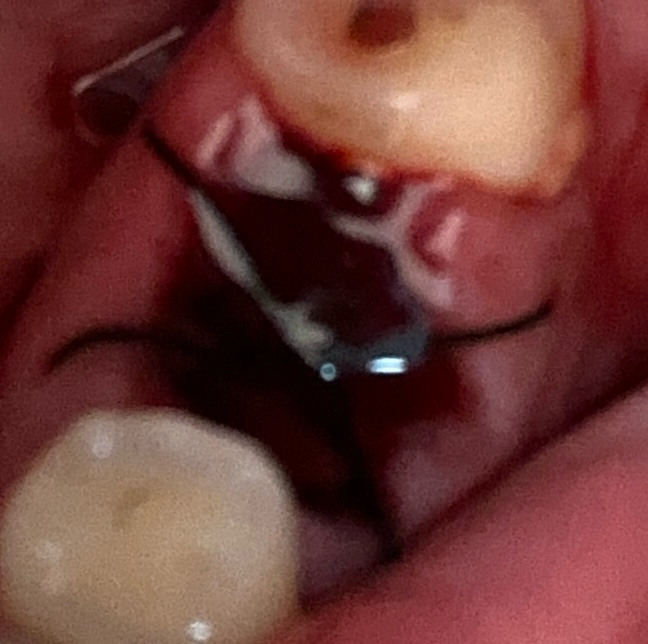

이를 뺀 자리에 검은 실처럼 묶여있네요

• 2번 째 사진

1. 봉합해둔 것은 발치 부위 잇몸이 벌어지지 않도록 한 것입니다